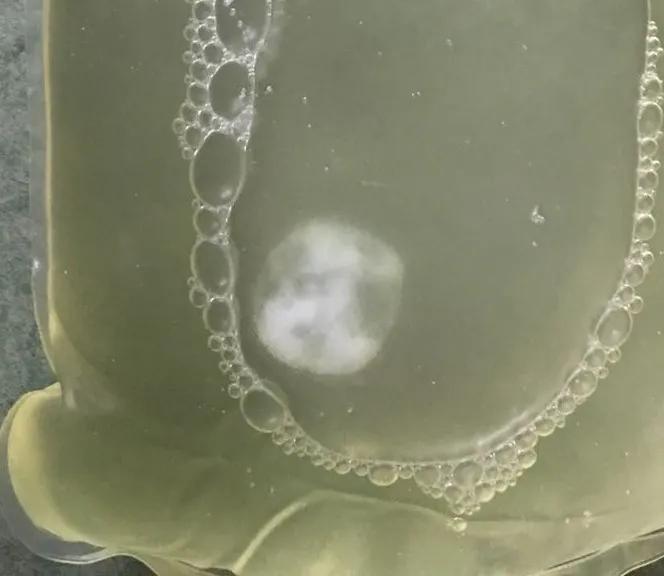

3、腹透液中出现团块状沉淀物

不伴有腹膜炎表现—联系我们在医护指导下腹透液中加肝素钠1250u。

伴有腹疼、腹透液混浊、发热等腹膜炎表现—联系医生立即来院!